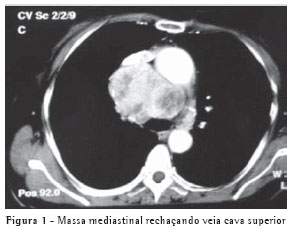

Uma paciente de 70 anos, sexo feminino, foi encaminhada ao Departamento de Cirurgia Torácica do Hospital do Câncer AC Camargo com o diagnóstico radiológico de alargamento mediastinal. Havia dez anos tinha sido submetida à hemitireoidectomia direita por nódulo tireoidiano benigno. O exame físico era normal, assim como a análise laboratorial, incluindo os hormônios tireoidianos. A tomografia computadorizada de tórax evidenciou massa de grandes proporções e contato íntimo com estruturas mediastinais (Figura 1), principalmente com a veia cava superior. Devido à possibilidade de invasão vascular foi realizada ressonância nuclear magnética do tórax, que excluiu invasão da veia cava superior.

A paciente foi submetida à anestesia geral com intubação seletiva e operada mediante toracotomia lateral direita, com acesso à cavidade torácica através do quarto espaço intercostal. O inventário da cavidade mostrava massa de grandes proporções lobulada e hipervascularizada, estendendo-se do mediastino superior até o pericárdio, comprimindo a veia cava superior (Figura 2). Houve certa dificuldade para liberação das aderências com a veia cava superior, principalmente junto ao pericárdio.